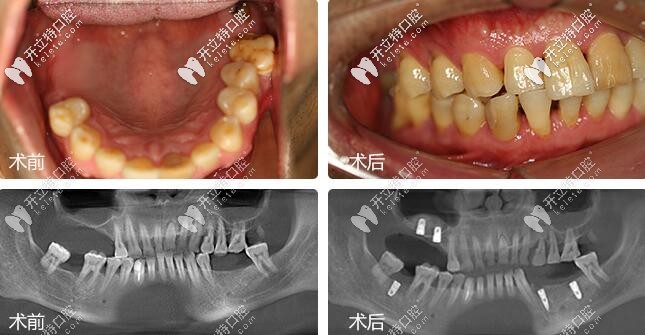

鄭蒼尚院長微創(chuàng)種植牙案例▼

深圳麥芽口腔鄭蒼尚院長微創(chuàng)種植牙案例